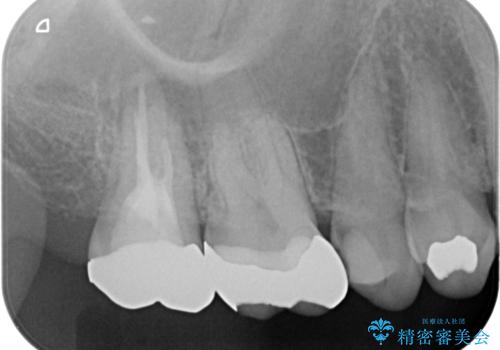

レントゲンと,CT撮影を行なったところ右上小臼歯が虫歯、右上第二大臼歯には根の先に大きな病気がありました。

根管治療はラバーダム防湿を行い、無菌的な状態で治療を行っています。

CTでは経過良好で経過観察を行なっていきます。